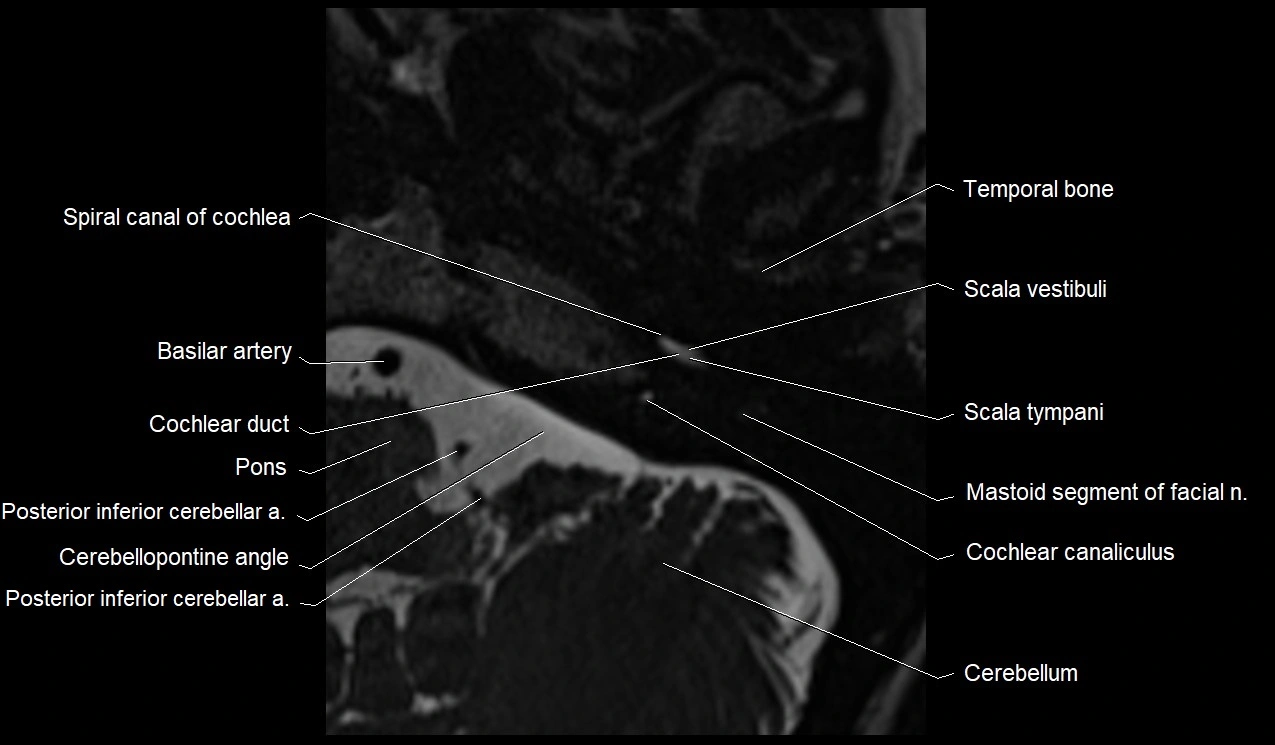

MRI Appearance

• The abducens nerve is a small, thin, linear structure

• Best visualized on high-resolution T2-weighted 3D MRI sequences (e.g., FIESTA or CISS)

• Seen as a hypointense (dark) line running from the brainstem at the pontomedullary junction, traversing the prepontine cistern, and entering Dorello’s canal under the petrosphenoidal ligament, then into the cavernous sinus, and finally the orbit

• May be challenging to visualize in standard MRI due to its small size

• Pathology may be inferred by absence, displacement, or enhancement of the nerve